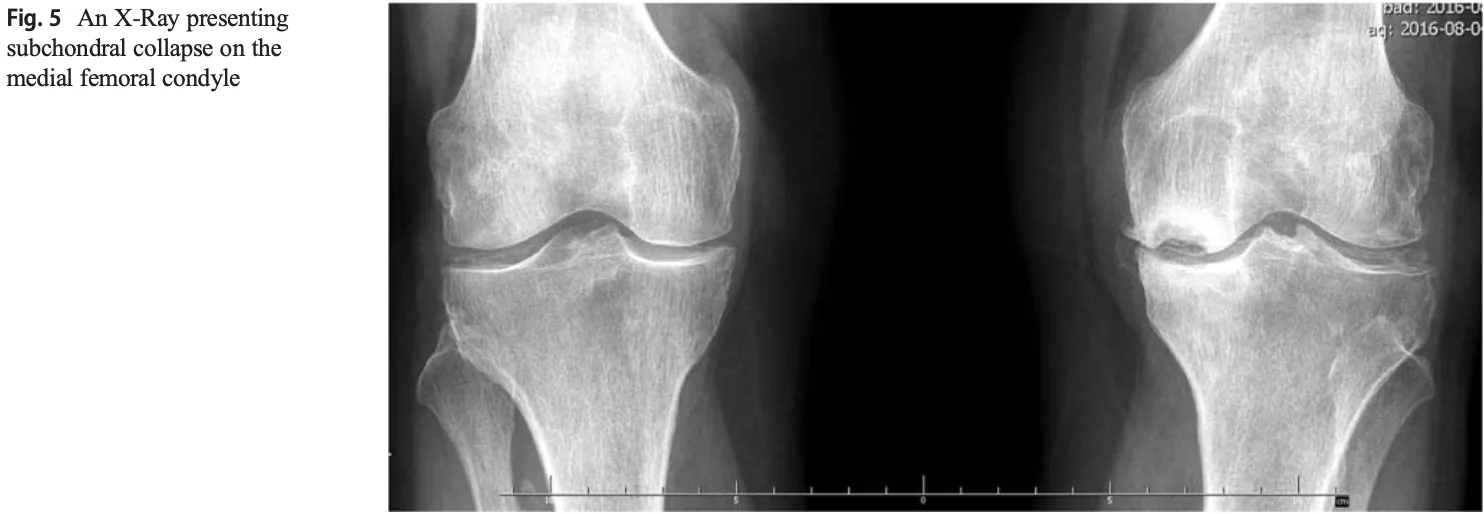

左の膝関節大腿骨内側部で骨が壊死した結果, 陥没しています.

その結果, 変形性膝関節症の所見に加え, 大腿骨内顆の陥没を認めました.

大腿骨内顆骨壊死とは, 大腿骨の膝関節の内側にあたる内顆部が血流不足などで死んでしまう病気で, 50歳以上の女性に多く, 突然の強い膝の痛みで発症するのが特徴です.

大腿骨内顆骨壊死と診断し, 精査目的にMRIを予約しました.